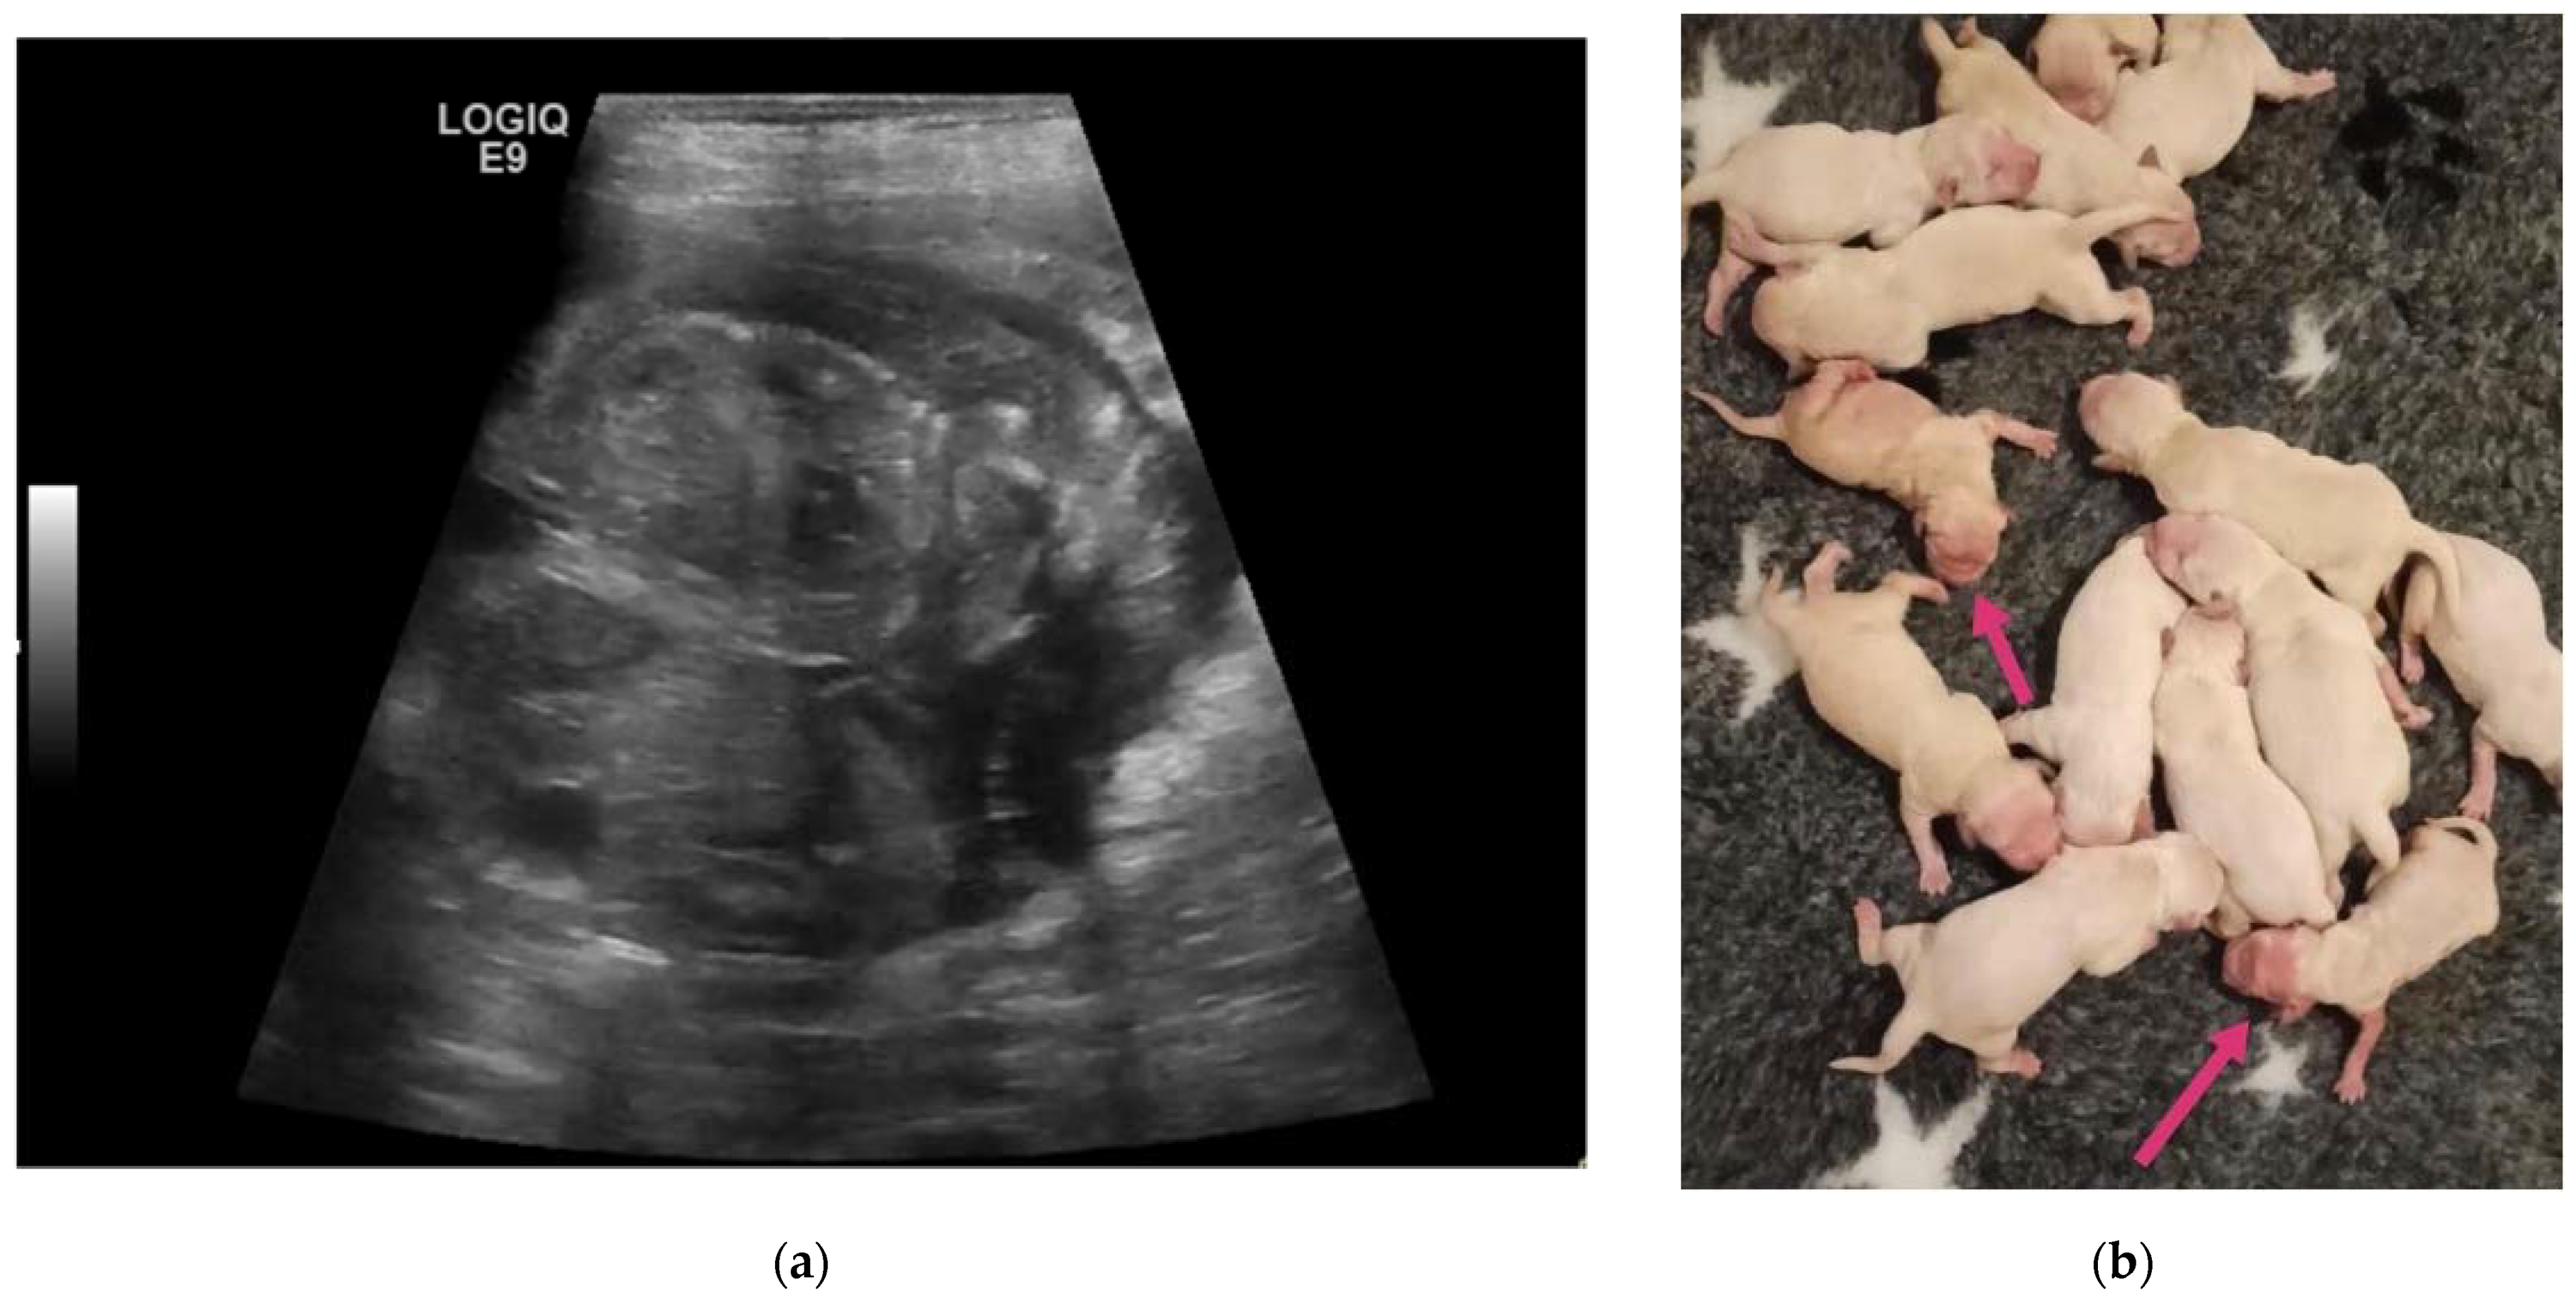

| 7C | 3-year-old Golden Retriever female dog | 50 | 14 | Monochorionic twins, morphologically comparable to the other foetuses. | C-section. Twins alive and of opposite sex, slightly dysmature. |